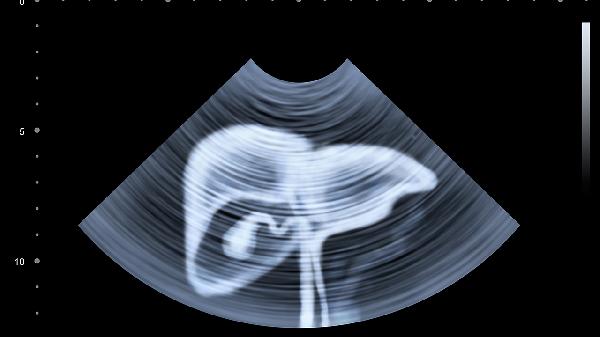

非酒精性脂肪肝与代谢综合征密切相关,肥胖人群发病率较高。早期表现为转氨酶轻度升高,超声显示肝实质回声增强。治疗首选二甲双胍缓释片改善胰岛素抵抗,配合水飞蓟宾胶囊护肝。需通过有氧运动减重,控制每日热量摄入,避免快速减肥导致肝损伤加重。